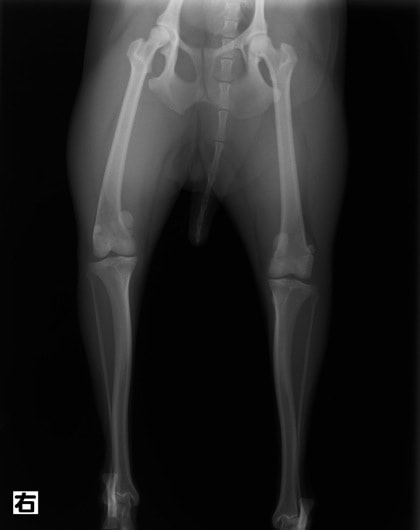

■ 症例24 キャバリア 7か月

左右膝蓋骨内方脱臼(左:グレードⅣ 右:グレードⅢ)

以前から左右後肢の跛行が認められ、整形外科学的検査・レントゲン検査により左右の膝蓋骨脱臼が認められた。症状が重度である左膝の膝蓋骨脱臼整復術を行った。外科手技は縫工筋及び内側広筋の解放、脛骨粗面の外側転位、滑車ブロック形造溝術、内外側関節方の縫縮を実施した。術後一か月時点で、左の膝蓋骨は安定しており経過は良好である。

本症例は成長期における重度の膝蓋骨脱臼であり、術後の再発の可能性もあるため、経過をしっかりと観察していく必要がある。また、今回手術を実施していない右膝に関しても経過を観察し、手術を検討していくこととする。